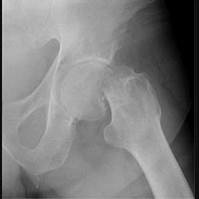

问题 图示骨折后,下列哪一体征不可能出现 ( )

选项 A、患肢略长于健肢 B、Shoemaker线相交于脐下 C、Bryant三角底边缩短 D、患肢外展、外旋、缩短畸形 E、髋部叩击痛

答案 A